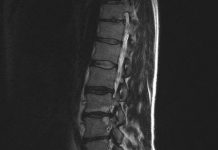

Nieuwe herniabehandeling (PTED) voorlopig vergoed

De afkorting staat voor Percutaan Transforminale Endoscopische Descectonomie. Dat betekent dat de zwelling van de hernia wordt verwijderd via je een klein sneetjeaan de...